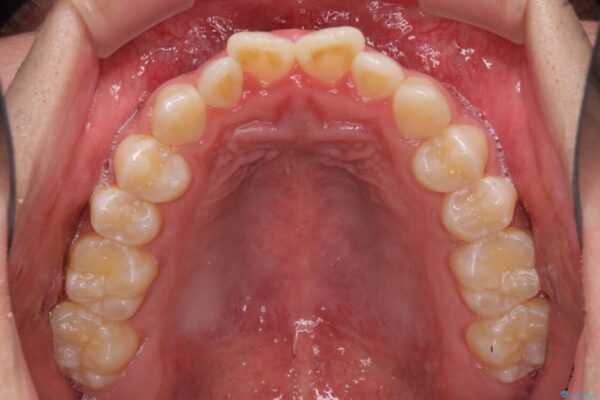

治療後

• 口元の突出感を改善 受け口傾向の咬み合わせの抜歯矯正 治療後画像